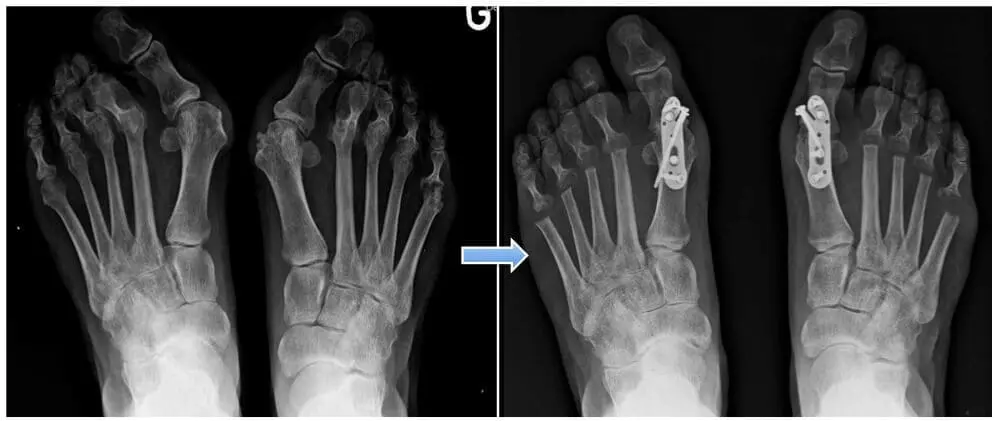

Association d’une déformation du gros orteil (Hallux valgus) et de douleur sous l’avant pied (métatarsalgie)

Si, malgré des chaussures confortables, vous n’avez pas encore commencé de traitement, il faut alors proposer des semelles orthopédiques afin de modifier les pressions de l’avant-pied ce qui soulagera vos douleurs. Nous optons le plus souvent pour des semelles entières, qui apportent souvent une meilleure stabilité. Parfois les semelles orthopédiques améliorent les douleurs plantaires mais en augmentant le volume dans la chaussure, la déformation du gros orteil aura moins de place et risque de devenir plus symptomatique et donc douloureux. Si les soins podologiques, de pédicure et les semelles soulage insuffisamment, une chirurgie est recommandable. Dans ce cadre, il est important de comprendre que le traitement de la métatarsalgie est indissociable de la déformation du gros orteil. Ce qui veut dire que le traitement de la métatarsalgie imposera la correction de l’hallux valgus, même si celui ci n’est pas à l’avant plan au niveau de votre plainte.

Dans cette situation, si le traitement conservateur par consigne de chaussage et semelle orthopédique n’a pas donné le résultat attendu, la correction du gros orteil et du reste de l’avant-pied sera indispensable.